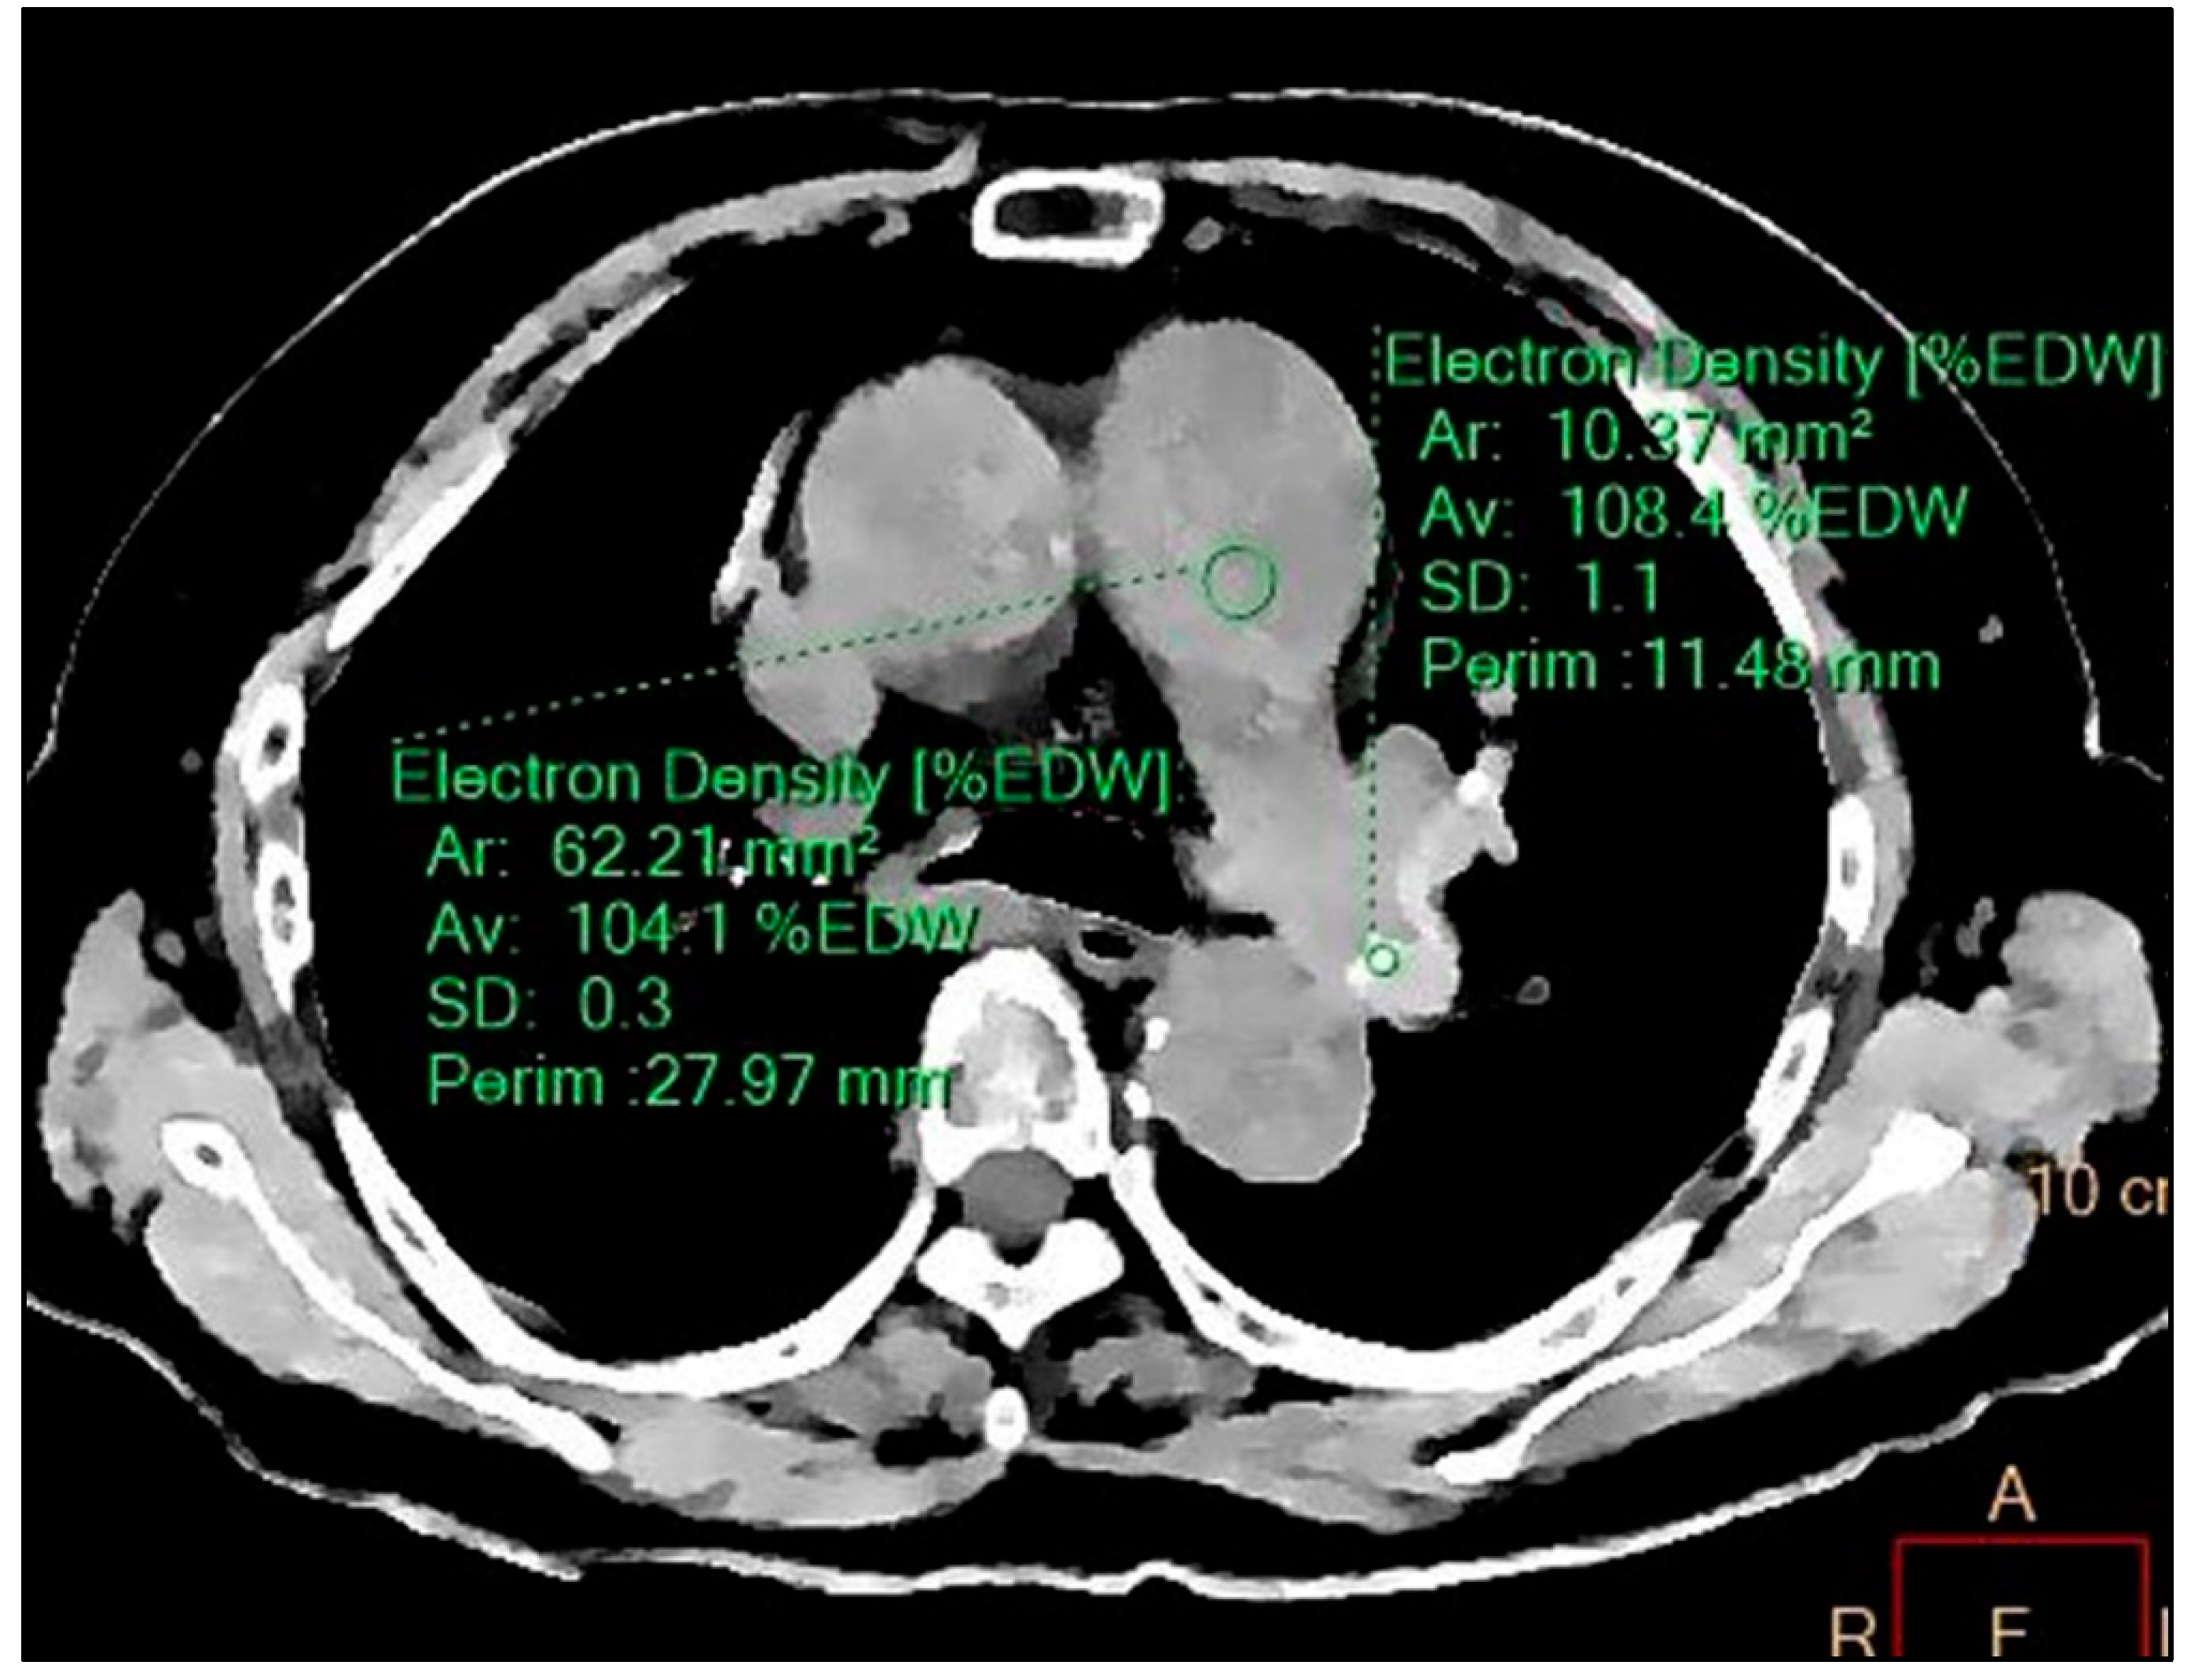

2. Case Report

3. Discussion